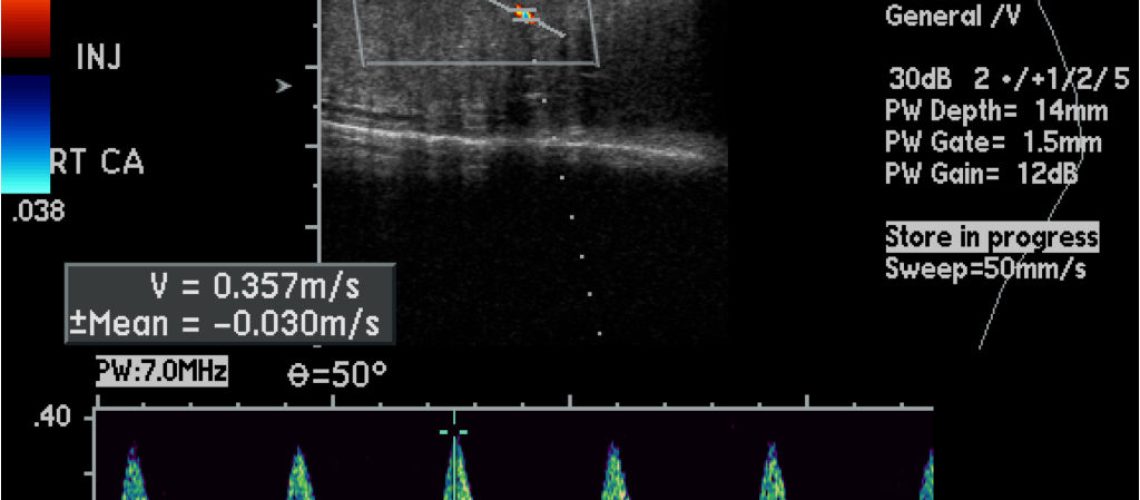

A disfunção erétil (DE) afeta muitos homens e pode ter diversas causas, desde fatores psicológicos até problemas vasculares. Para um diagnóstico preciso, um dos exames mais eficazes é o ultrassom Doppler Peniano com fármaco indução, que avalia o fluxo sanguíneo no pênis e a resposta vascular à ereção. Além disso, em alguns casos, o tratamento com injeções intracavernosas pode ser uma solução eficaz para restaurar a função erétil.

Esse exame é um método invasivo que analisa a circulação sanguínea nos corpos cavernosos do pênis. Ele é feito em duas etapas:

1. Medição inicial do fluxo sanguíneo – o pênis é avaliado em estado de repouso para verificar a circulação basal.

2. Indução farmacológica da ereção – um medicamento vasodilatador (como a prostaglandina E1 ou um conjunto de medicações) é injetado no corpo cavernoso para estimular a ereção, permitindo a análise do fluxo arterial e do retorno venoso.